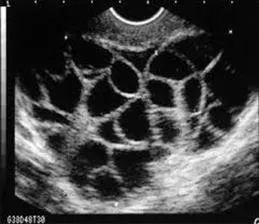

取卵的方法如下图,在超声的引导下,用长针穿过阴道壁,直接伸到卵巢,再将成熟的卵子一颗颗抽出。④

【卵巢过度刺激综合征】大部分正常生育年龄女性,每个月经周期仅排卵1个成熟卵子。

而这些灰色机构,为了让一次取卵获得二三十个甚至更多卵子,会让“卵妹”们打促排针,促使卵细胞成熟。随之而来的潜在的风险就是“卵巢过度刺激综合征”。

充满卵泡的卵巢患有“卵巢过度刺激综合征”的女性,可能会有不同程度的腹胀、恶心、呕吐、腹泻、体重快速增加、少尿或无尿、血液浓缩、血容量不足、电解质紊乱、胸腔积液、心包积液、腹腔积液、呼吸窘迫综合征,伴血栓形成倾向的高凝状态及多器官功能衰竭。④